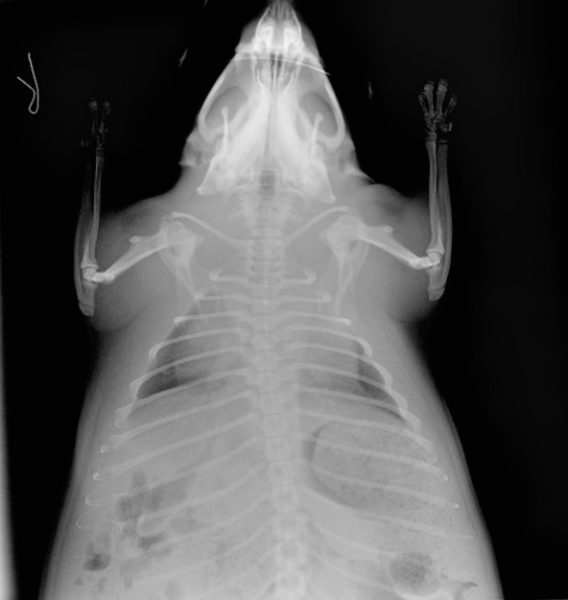

There were minor bite wounds consistent with a dog attack and radiographs showed what we suspected at the time to be a significantly enlarged heart.

They also showed fluid-filled lungs. There was free fluid in the abdomen as well.

Our team was shocked to find a large abscess within the pericardial sac that was similar in size to the heart itself. This is what caused the heart to appear so large on radiographs.

The fluid in the abdomen was associated with a severe inflammation of the gastrointestinal tract. There were multiple other signs of sepsis and secondary coagulation issues throughout the beaver’s body and this led to failure of multiple organs.